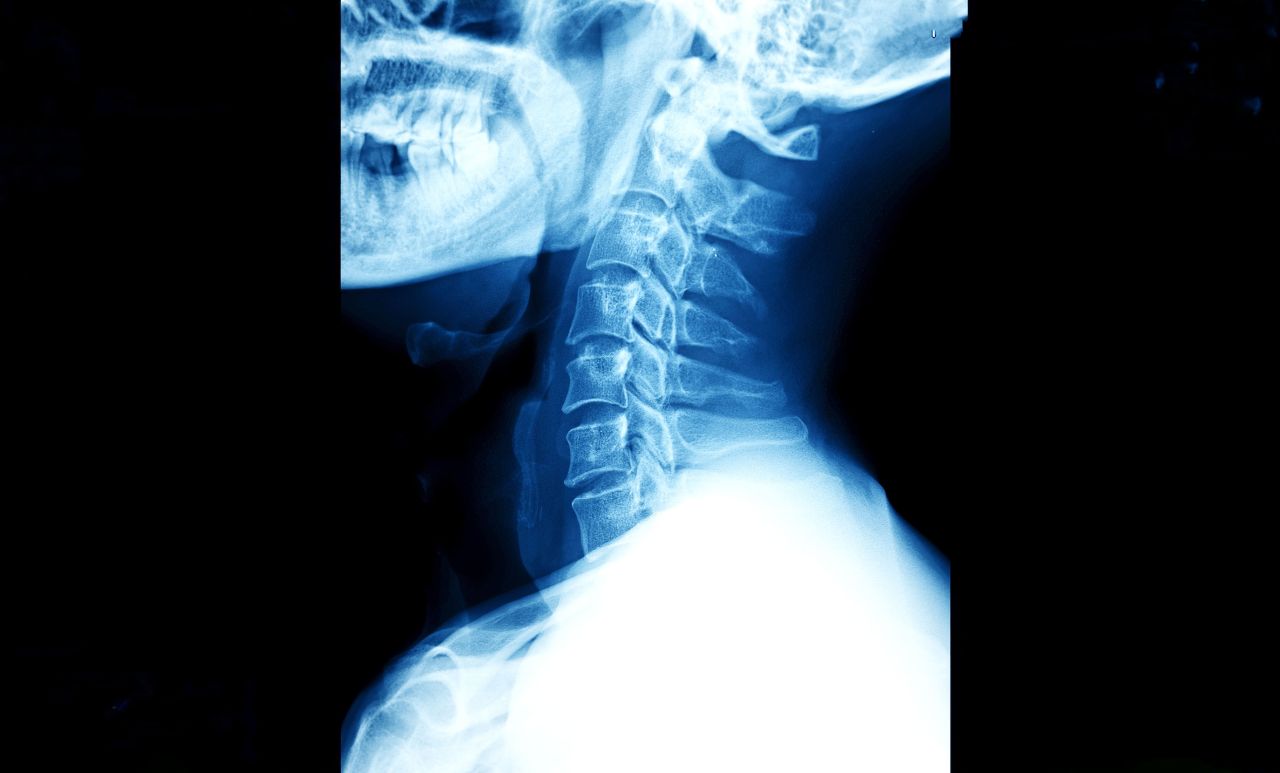

Cervical Disc Surgery: Replacement vs. Fusion for Neck Pain

If you have a herniated disc in your neck, you know the feeling: the constant ache in your neck, the electric shocks down your arm, the numbness in your fingers that makes buttoning a shirt impossible.

When physical therapy and injections stop working, surgery becomes the conversation. For decades, the "gold standard" was to fuse the bones together (ACDF). But today, active patients in New York have a better option: Artificial Disc Replacement (ADR).